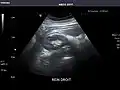

Kidneys: Right and left kidneys measure 11.5 cm and 12 cm in length respectively. No hydronephrosis. Small left lower pole kidney cyst.

Right kidney -